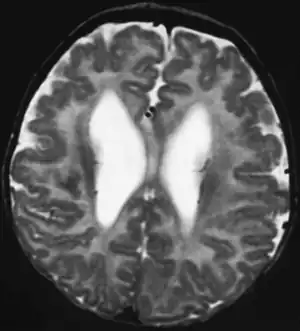

| This child presented with seizures. The coronal true inversion recovery sequence shows thickened and disordered cortex in superior frontal and cingulate gyri bilaterally (arrow). There are small convolutions visible at the corticomedullary junction. The appearance is that of cortical dysplasia, with polymicrogyria more likely than pachygyria due to the small convolutions visible. There are also small foci of grey matter signal in the corpus callosum, deep to the dysplastic cortex (double arrows). These probably represent areas of grey matter heterotopia. | |